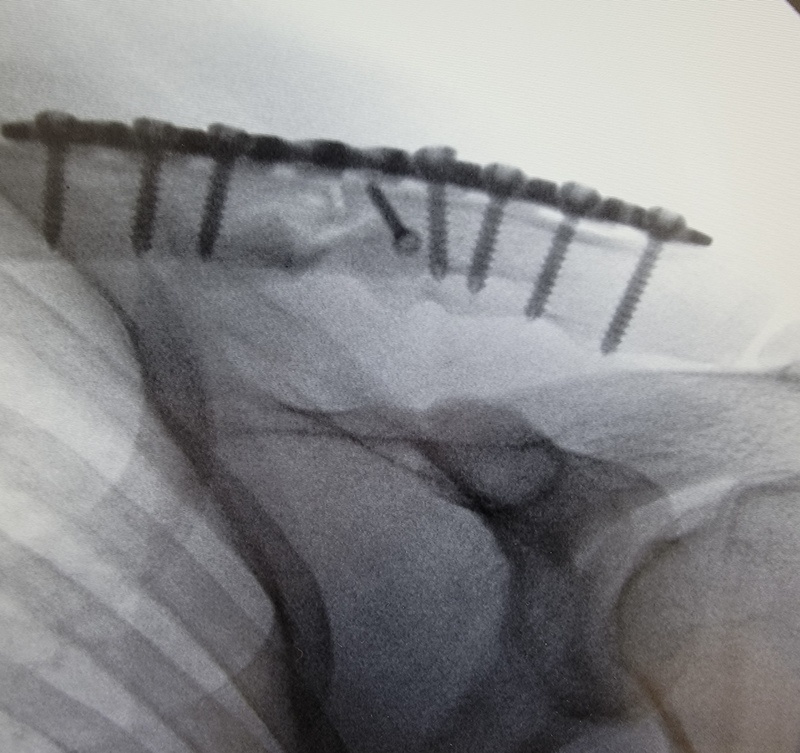

- Tibial Plateau Plate